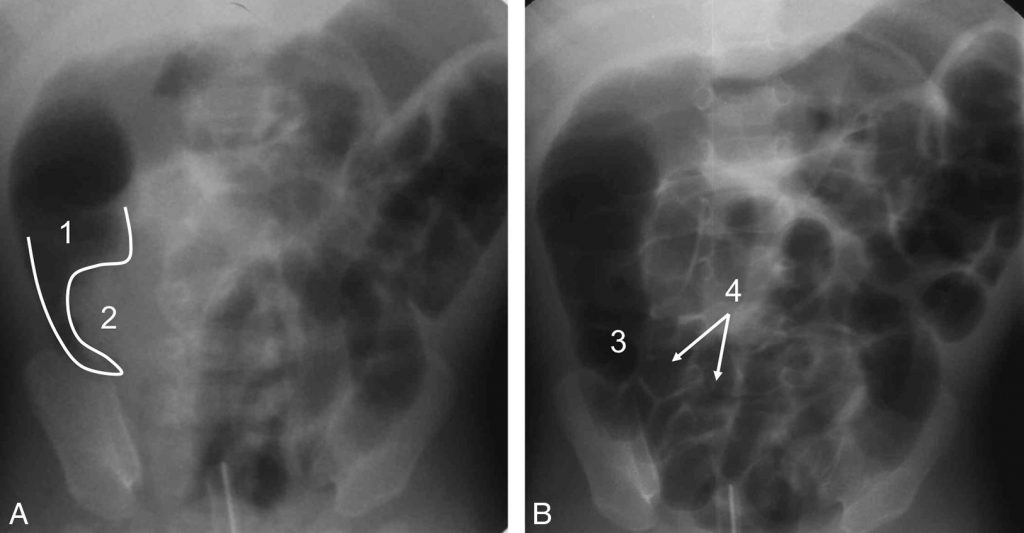

L’échographie permet en coupe transversale (perpendiculaire à l’axe du tube digestif exploré) la visualisation d’une image en « cocarde » composée de l’anse recevant l’invagination et de l’anse invaginée (figure 103.1A) et en coupe longitudinale (dans l’axe du segment de tube digestif exploré) la visualisation d’une image en « sandwich » (figure 103.1B).

Fig. 103.1. Échographie abdominale : visualisation de l’anse recevant l’invagination (1) et de l’anse invaginée (2).

Coupe transversale (A), image en « cocarde ». Coupe longitudinale (B), image en « sandwich ».

Fig. 103.2. Lavement pneumatique.

(A) L’aspect en « pince de homard » est dû à l’air (1) qui moule la tête du boudin d’invagination (2). (B) L’invagination est réduite. Le cæcum est en place et de morphologie normale (3). Les dernières anses sont largement remplies d’air (4).

Source : CERF, CNEBMN, 2022.